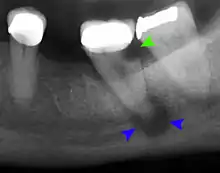

Transillumination demonstrating fracture Decay (green) with apical abscess (blue)

Decay (green) with apical abscess (blue) Gutta-percha point indicating abscess origin

Gutta-percha point indicating abscess origin